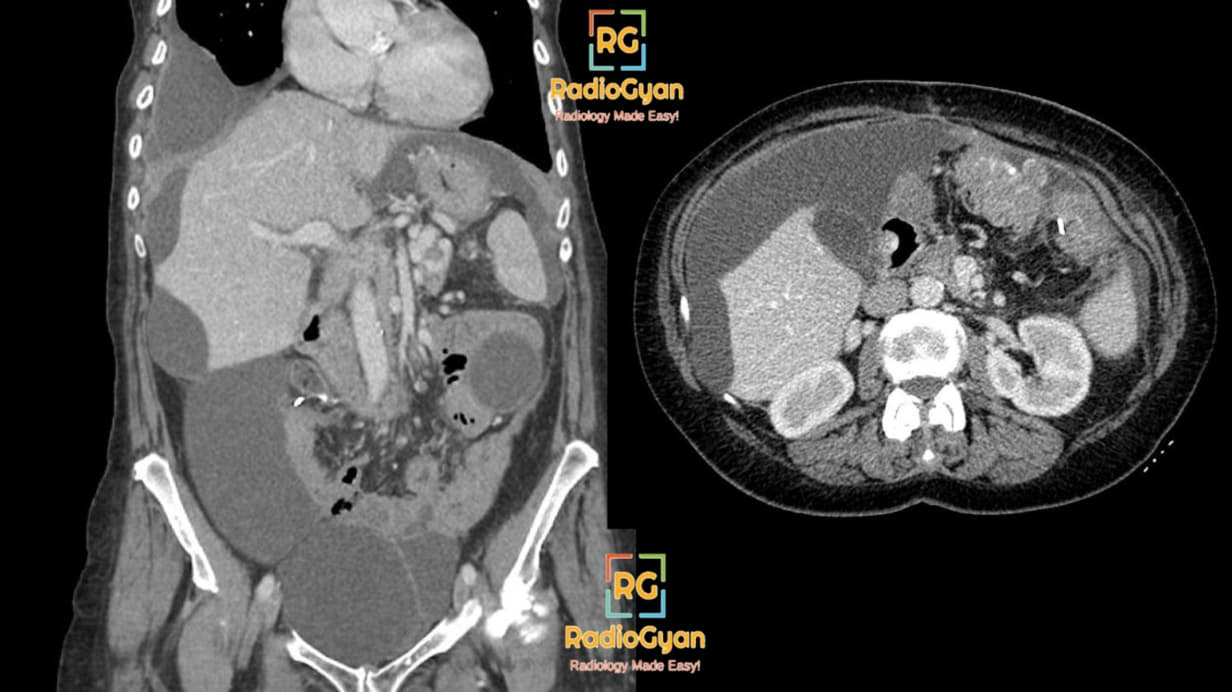

Frontiers Case report Rare isolated cystic hepatic metastasis of a Iih Radiology Case Idiopathic intracranial hypertension (iih), also known as pseudotumor cerebri, is a neurological disorder characterized by high. The diagnostic criteria for iih are based on clinical signs and symptoms, as well as on mri findings and the measurement of csf. This case demonstrates some of the key features of idiopathic intracranial hypertension (iih): Idiopathic intracranial hypertension (iih) is defined as a. Iih Radiology Case.

From radiogyan.com

Classic Radiology Cases 3 Spotters Set 57 RadioGyan Iih Radiology Case Dilated csf spaces around the optic nerves. This case demonstrates some of the key features of idiopathic intracranial hypertension (iih): Idiopathic intracranial hypertension (iih), also known as pseudotumor cerebri, is a neurological disorder characterized by high. Advances in ophthalmic diagnostics and results of interventional clinical trials are shifting diagnosis and management of idiopathic intracranial. Idiopathic intracranial hypertension (iih) is defined. Iih Radiology Case.

Radiology Cases RadioGyan Iih Radiology Case The diagnostic criteria for iih are based on clinical signs and symptoms, as well as on mri findings and the measurement of csf. Dilated csf spaces around the optic nerves. Idiopathic intracranial hypertension (iih) is defined as a syndrome of raised intracranial pressure with normal imaging of the brain and cerebrospinal. This case demonstrates some of the key features of. Iih Radiology Case.

Classic Radiology Cases 2 Spotters Set 56 RadioGyan Iih Radiology Case Advances in ophthalmic diagnostics and results of interventional clinical trials are shifting diagnosis and management of idiopathic intracranial. Idiopathic intracranial hypertension (iih), also known as pseudotumor cerebri, is a neurological disorder characterized by high. Idiopathic intracranial hypertension (iih) is defined as a syndrome of raised intracranial pressure with normal imaging of the brain and cerebrospinal. Dilated csf spaces around the. Iih Radiology Case.